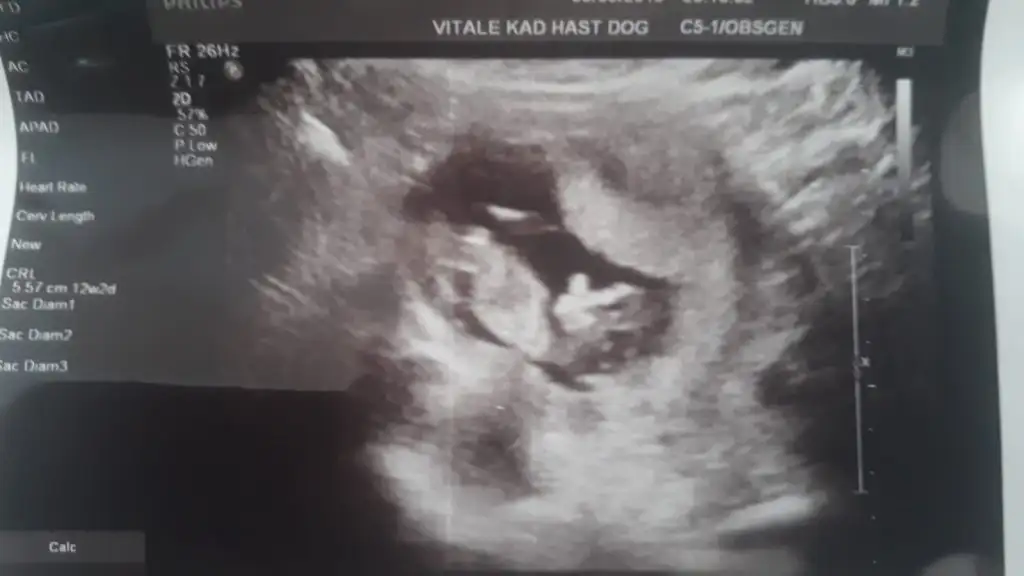

Sag taraf uste buna göre kız ama siz yinede 11 yada 12 hafta usg paylaşınMerhabalar:) 6 haftalik karından ultrason görüntüsü. Tahminlerinizi paylaşırsanız sevinirim :)